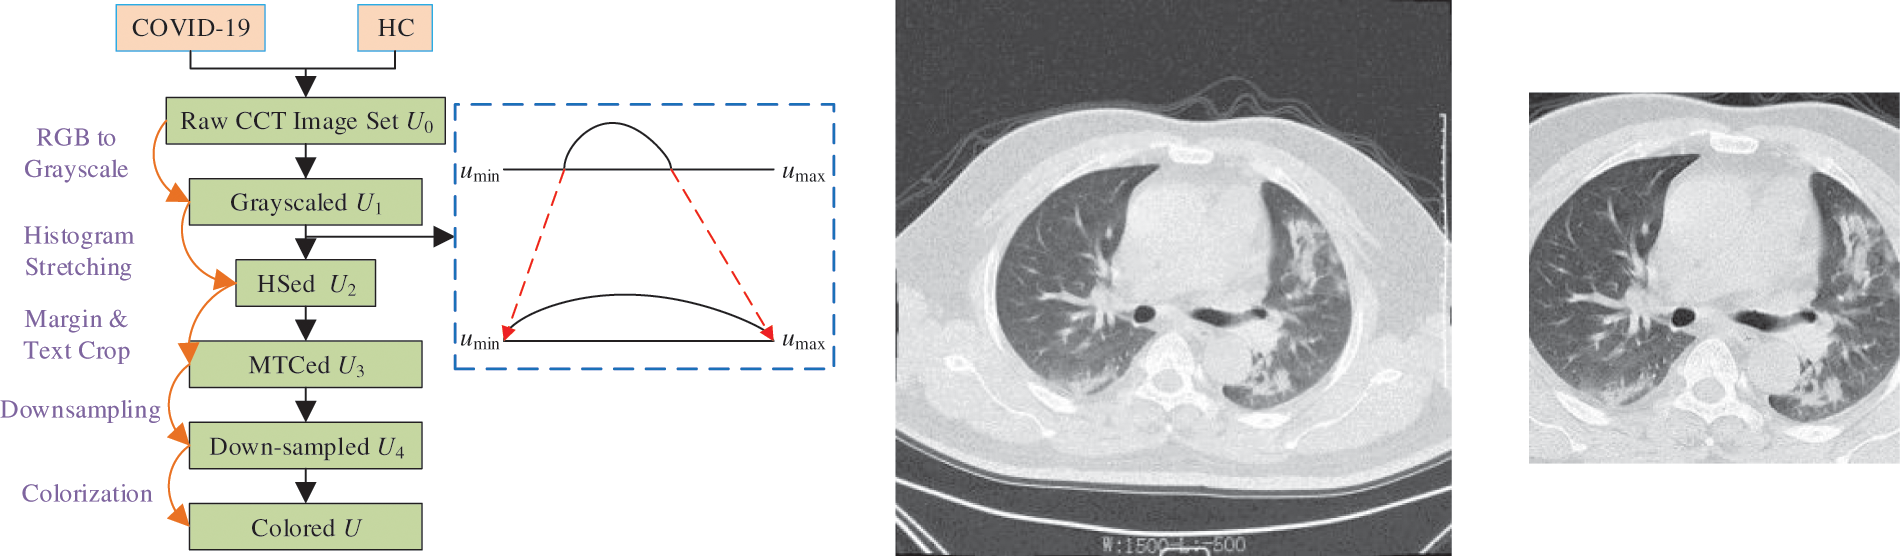

A five-step preprocessing is employed. The flowchart can be seen in Fig. 1a, in which the five steps are grayscaling, histogram stretching (HS), margin and text crop (MTC), downsampling (DS), and coloriazation. Here U stands for the dataset at each step. HS is used to enhance the contrast. Suppose

Figure 1: Preprocessing

The hyperparameters are listed in Table 3. The minimum and maximum gray values of HSed images are